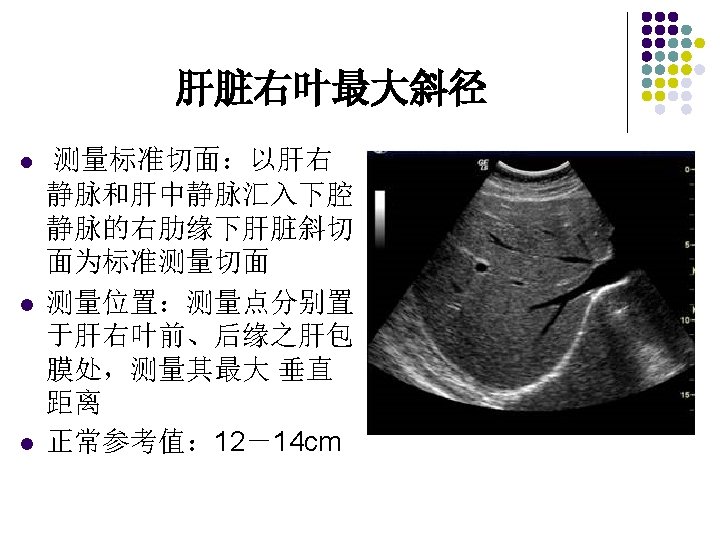

肋缘下斜切声像图 The fourth scan should show the right portal vein as it divides into the anterior and posterior segments of the right lobe of the liver. The gallbladder may be seen in this scan as an anechoic structure medial to the right lobe and anterior to the right kidney.